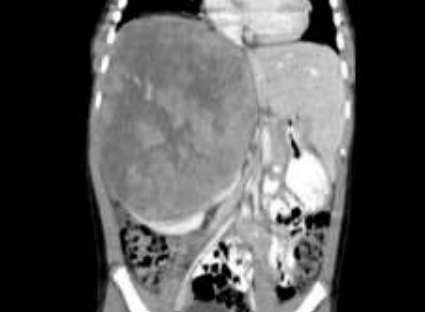

Menino, 5 anos, negro, admitido no Pronto Socorro com a queixa de aumento do volume abdominal, sem dor ou demais sintomas associados. Realizada Tomografia Computadorizada de abdome que evidencia a seguinte imagem:

Coletadas catecolaminas urinárias com VMA=10 e VMA=15.